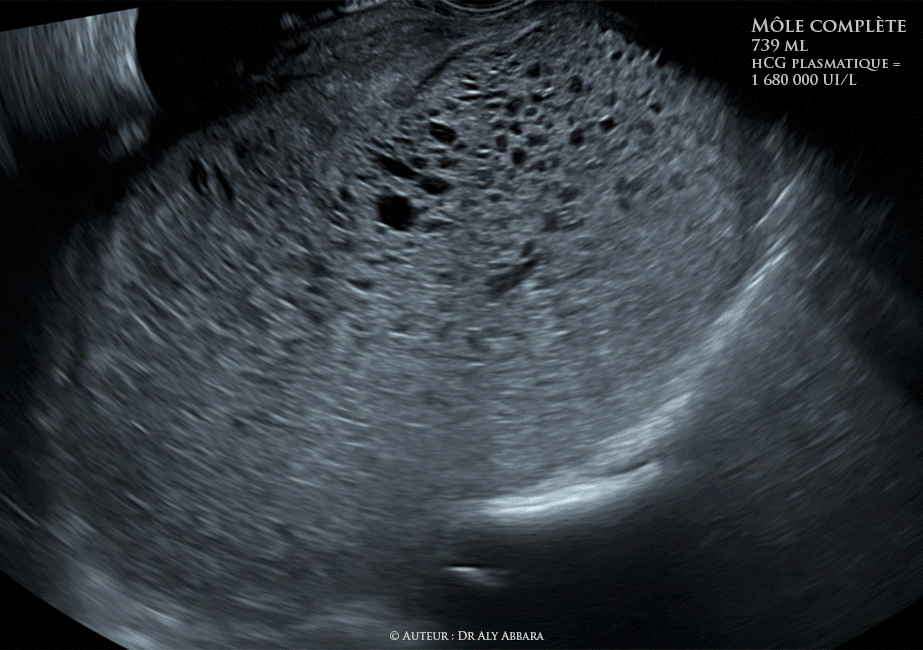

Grossesse môlaire (môle complète) de 739 ml de volume - Aspect échographique et clinique - الحمل العداري أو الرحى العدارية

Images échographiques animées montrant l'aspect ultrasonique d'une grossesse môlaire de type môle complète :

I- Une cavité utérine occupée par une structure tissulaire, hétéroéchogène, plutôt vésiculaire d'environ 739 ml de volume, soit 142.5 x 93.5 x 105.9 mm de diamètre.

II- Aucun élément anatomique embryonnaire ou fœtal reconnaissable.

III- Pas de vésicule vitelline.

IV- Pas de cavité amniotique.

Le taux de β-hCG plasmatique le jour de la réalisation de ces images était égal à 1 680 000 UI/l.

La conclusion : aspects cliniques et histologiques évocateurs d'une môle complète.